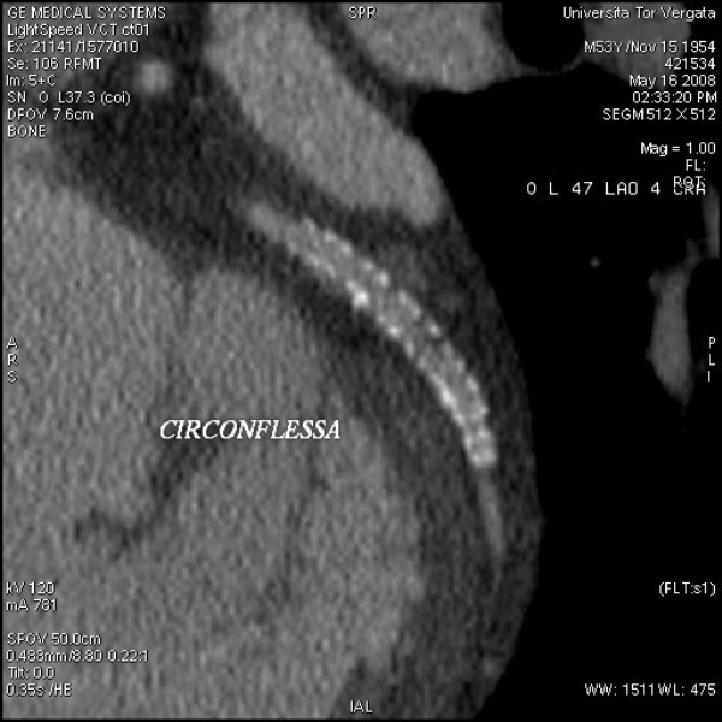

Figura 2 Esempio di stent coronarico su circonflessa che alla valutazione con TC risulta pervio

Negli ultimi 25 anni l’angioplastica percutanea si è imposta come principale forma di rivascolarizzazione coronarica rispetto al trattamento chirurgico di bypass aorto coronarico, in particolare per le patologie monovasali. La prevalenza di Pazienti sottoposti a trattamenti coronarici di tipo percutaneo (PCI) nel nostro Paese è di circa mezzo milione con il 70% di tali procedure rappresentate da stenting. Tuttavia durante i primi 6 mesi dal trattamento una percentuale di Pazienti variabile tra l’11% e il 46% va incontro a restenosi intra-stent, risultando quindi fondamentale uno stretto monitoraggio post-trattamento.

Attualmente la TC volumetrica multistrato (TCMS), ed in particolare l’uso di scanner a 64 file di detettori, rappresenta una valida alternativa all’angiografia coronarica nel follow-up di questi Pazienti. Pur essendo i risultati incoraggianti, la valutazione della pervietà degli stent, risulta in alcuni casi parzialmente inficiata da artefatti correlabili alla struttura metallica, alle dimensioni ed alla diversa geometria.

L’importanza degli artefatti cambia in relazione al tipo di metallo ed al design del stent, ad esempio stent costituiti di tantalium come il Wiktor, talvolta rendono impossibile la visualizzazione del lume oppure altri device aventi spessore delle maglie > 0.14 mm come il Bx Sonic o il NIR possono causare severi artefatti da blooming, dovuto all’indurimento del fascio di raggi X durante il passaggio attraverso le maglie metalliche dello stent. A causa della presenza di tale artefatto, i valori di attenuazione ottenuti, possono risultare maggiori all’interno del lume rispetto a quelli misurati nel vaso prossimalmente al device; tuttavia questa differenza si può ridurre con l’utilizzo di filtri di convoluzione (kernel) come il detail e il bone.

Anche il calibro ridotto degli stent è stato fino ad oggi da molti considerato responsabile della scarsa valutabilità del lume dello stent in relazione all’artefatto da blooming. Tuttavia, con macchinari a 64 strati si è riusciti ad avere una visibilità ottimale anche in stent con diametro inferiore a 2.5 mm.

Nonostante questi limiti l’accuratezza diagnostica nella valutazione della re-stenosi intrastent con TC multidetettore di ultima generazione si mostra elevata; in un nostro studio con TC 64 strati su 402 stent, l’identificazione di stenosi intrastent ha dato valori statistici di sensibilità del 94.9%, specificità del 98%, VPP del 94.2% e VPN del 98.3%.

Questi risultati, che si riscontrano anche in letteratura, fanno assumere alla TC 64 strati un ruolo rilevante nei Pazienti sottoposti a stenting coronarico, nell’indirizzare in modo corretto l’algoritmo diagnostico verso l’eventuale esecuzione di un esame invasivo come la coronarografia convenzionale.